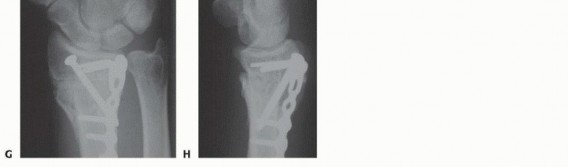

** Intra-articular Distal Radius Osteotomy **Intra-articular osteotomy should be attempted only when there is a simple fracture line that can be clearly identified by direct visualization as well as under image intensification ( TECH FIG 6A-C). Incompletely healed fractures (fewer than 3 to 4 months since injury) are ideal. Depending on the locations of the malunited articular fragments, perform either a dorsal or a volar exposure in the manner detailed earlier. When a dorsal exposure is used, a transverse capsulotomy allows access to the joint and monitoring of the articular osteotomy and realignment. In the case of a volar exposure, the capsule is not incised, but articular exposure may be possible through the osteotomy site. The osteotomy should recreate the original fracture line. This is monitored directly and under image intensification. Reduction is accomplished by soft tissue release and direct fragment manipulation. For many malunions, it is necessary to remove bone or callus from the fracture site to realign the fracture fragment. Callus or bone is removed until the fracture fragment fits properly ( TECH FIG 6D). Provisional Kirschner wires are used to hold the reduction ( TECH FIG 6E,F). The implants are then applied. Dorsally, a single T- or Pi-shaped plate or two 2.0- or 2.4-mm plates (one applied dorsally, ulnar to the tubercle of Lister, and the other applied radially between the first and second dorsal compartments) can be used ( TECH FIG 6G,H). Volarly, a T-shaped plate is usually used. After final plate fixation, provisional fixation is removed. This entire process is monitored using image intensification to confirm appropriate osteotomy site, correction of alignment, and implant placement. Deflate the tourniquet, close the wound, and apply the splint in the manner detailed earlier. 150

### TECH FIG 6 • A-C. PA and lateral radiographs and CT of an intra-articular dorsally angulated malunion. D. A Freer elevator is used under fluoroscopy to reposition the articular fragment. E,F. Intraoperative fluoroscopic views showing provisional correction and fixation. G,H. Final plate and screw fixation. (Copyright Diego Fernandez, MD, PhD.)